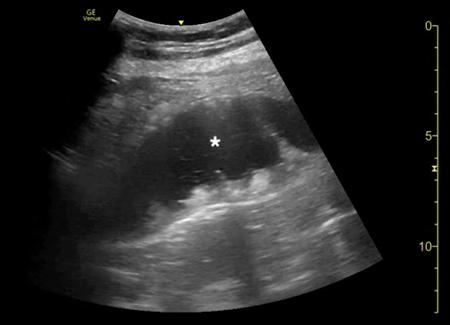

腹部床旁超声检查(POCUS)显示,胃部扩张并充满液体,高度疑似梗阻(图1,2)。

(图1 POCUS检查显示胃部膨胀充满液体[星号])

随后患者进行紧急进行外科会诊评估。多次尝试放置鼻胃管,最终放置成功后引流非胆汁性胃内容物 2,000 ml,重复进行POCUS检查证实胃减压(图6)。

当怀疑有胃扭转时,选择初始的影像学检查非常重要,因为诊断延迟可能导致致命的并发症。CT检查高度可靠,主要有两种表现,即正常的胃窦幽门移行区和胃窦位置异常,诊断急性胃扭转的敏感性和特异性均为100%。POCUS是一种有效的非侵入性影像检查方式,主要用于床旁评估。此外,POCUS无辐射,并可根据临床情况随时进行重复检查。本例患者POCUS检查显示,胃部严重扩张,胃内容物分层,类似胃出口梗阻(GOO)的“黑白饼干”征象。POCUS还可以用来动态观察胃减压成功与否。